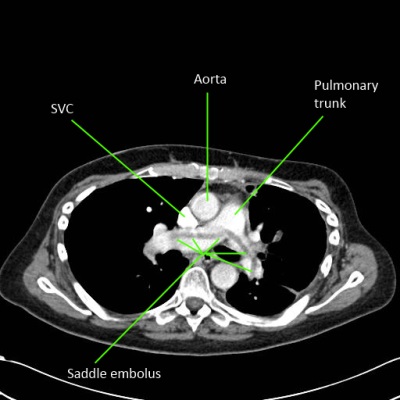

CTPA

- peripheral emboli affecting subsegmental arteries may be missed